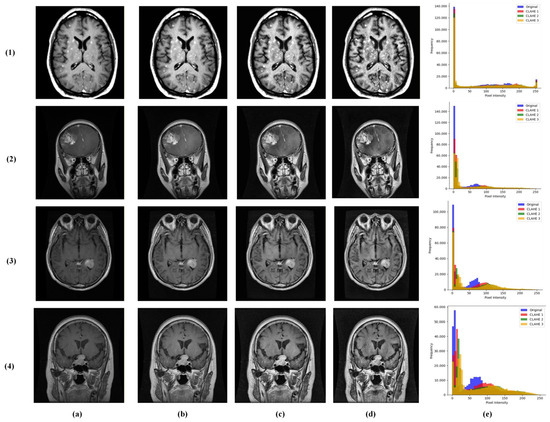

We introduced a multi-contrast CLAHE enhancement strategy implemented using the OpenCV library [23]. Each grayscale MRI was processed through the following three CLAHE configurations: conservative (clipLimit = 1.0, grid = 4 × 4), moderate (clipLimit = 2.0, grid = 8 × 8), and aggressive (clipLimit = 3.0, grid = 12 × 12). These were stacked as separate channels, providing the model with complementary contrast perspectives for robust feature learning (Figure 3).

Figure 3.

Visualization of multi-contrast CLAHE preprocessing results across the following brain tumor classes: (1) no tumor, (2) glioma, (3) meningioma, and (4) pituitary tumor. Columns represent (a) original input MRI, (b) conservative CLAHE, (c) moderate CLAHE, (d) aggressive CLAHE, and (e) histogram.

Multi-contrast images were resized to 256 × 256 pixels (bilinear interpolation) and normalized, while masks used the nearest-neighbor interpolation. The dataset was divided at the patient level into 70% training, 10% validation, and 20% testing sets, maintaining class distribution. This comprehensive annotation supports integrated multi-task learning for simultaneous tumor classification and segmentation.